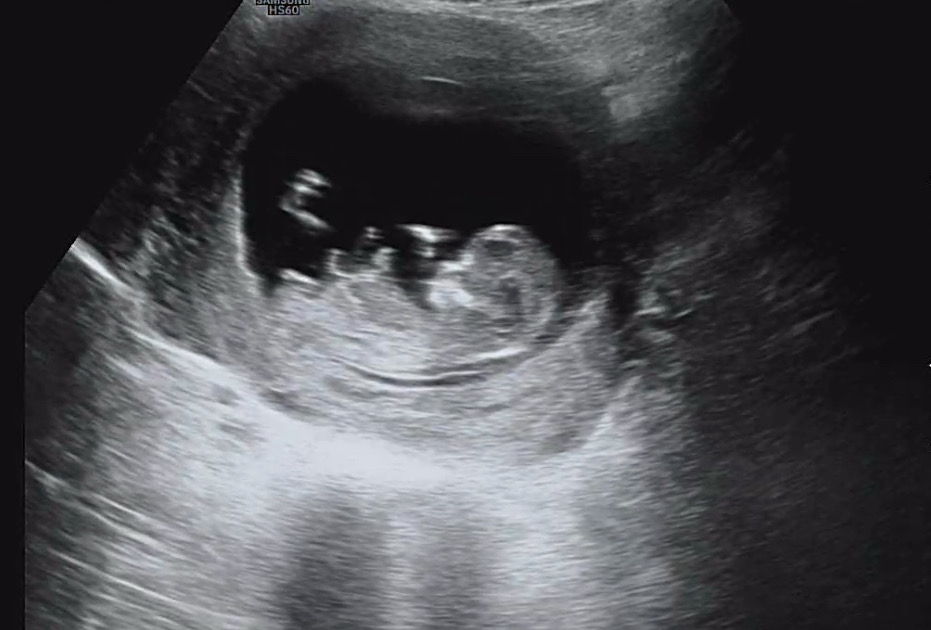

12주 딸인지 아들인지 궁금해요!!

각도법 부탁드릴게요!